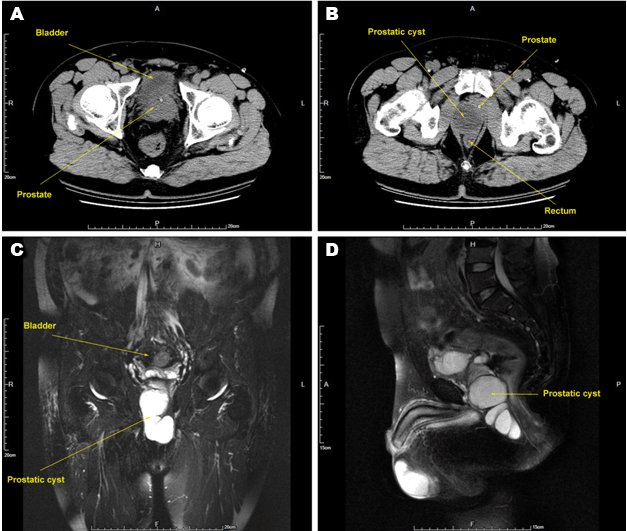

To further confirm the diagnosis, the patient received PSA test, CT scan, MRI scan and transrectal ultrasound-guided aspiration of prostatic cyst. Patient's PSA test was negative. CT scan demonstrated that there was a 4.5 x 4.2 cm of even hypodense shadow behind prostate gland resulting in pushing prostate gland to front left. Patient's prostate gland was enlarged with smooth boundary a href="#figure1"> (Figure 1A-B). MRI scan showed there were irregularly a long T1 and T2 signals (9.2 x 4.9 cm) near the right peripheral leaves and penis cavernous part which extended to perineum and rectum (a href="#figure1"> (Figure 1C-D). a href="#figure1"> Figure 1 showing that surrounding tissues were compressed and displaced. We performed transrectal ultrasound-guided aspiration of prostatic cyst and collected 15 ml of viscous milky fluid, which contained many epithelial cells and no sperm and no cancer cells. Bacterial cultures were negative.

Figure 1: Images of computer tomography (CT) scan and magnetic resonance imaging (MRI) scan. (A, B) computed tomography (CT) scan which showing that a 4.5 x 4.2 cm of even hypodense shadow is behind prostate gland and pushes prostate gland to front left. The prostate gland is enlarged with smooth boundary. (C, D) MRI scan showing there is irregularly a long T1 and T2 signals (9.2 x 4.9 cm) near the right peripheral leaves and penis cavernous part which extended to perineum and rectum.